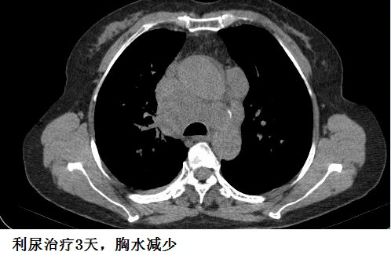

下面的图示,可以帮助大家加深印象!

另外,胸水的病因有时候很难准确判断,最初觉得可能不是心力衰竭引起的,但经验性治疗后,胸水有可能很快减少,这时候贸然按照之前的影像学资料去抽胸水,有可能“干抽”。

这个患者的胸水,应该是心包积液导致静脉回流受阻,体循环淤血引起的。利尿治疗后,胸水减少。